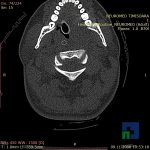

- Diagnosticul fracturilor:

- Unice

- Multiple

- Cu înfundare

- Complexe cranio-sinusale

- Complexe cranio-etmoidale

- Complexe cranio-orbitare

- Complexe cranio-faciale